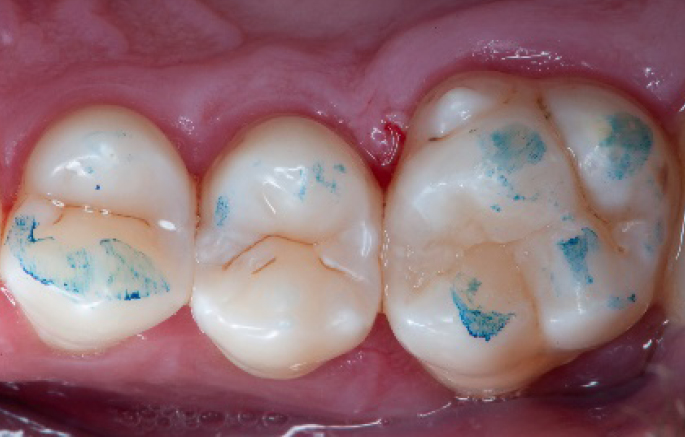

Initial situation of the patient

The patient came for a routine control appointment. She didn‘t report any symptoms but some bleeding during brushing.

Initial situation: an old class I composite restoration on 1.6. New caries on the mesial wall. Presence of plaque and inflammation.

• On the x-ray examination, a mesial translucency (initial caries) was found on tooth 1.6.

• The tooth presented an old class I composite restoration.

• Marginal inflammation and plaque were present.

• No symptoms were referred by the patient.